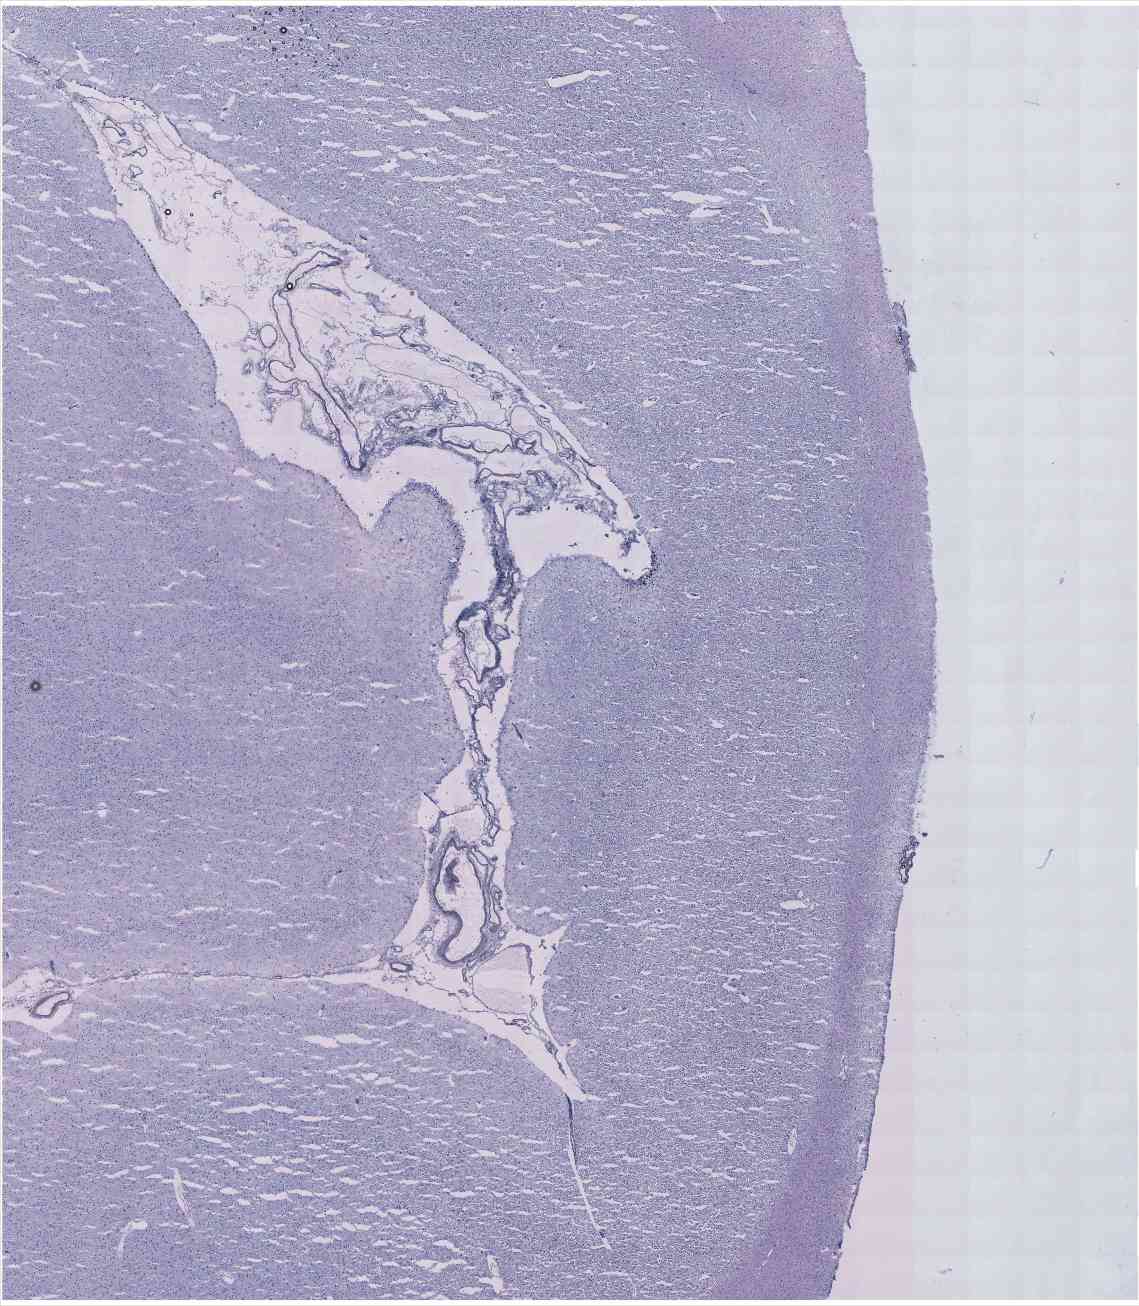

Chip 041 Well D2